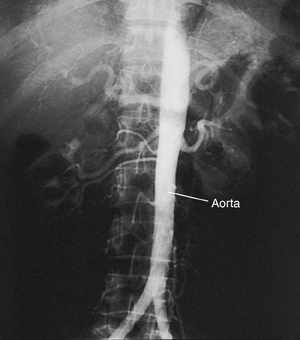

An aortic angiogram is a test that takes pictures of the aorta. This is the main blood vessel that carries blood from your heart to the rest of your body. The test can show problems with your aorta. These include a blockage or an aneurysm (a balloon-like bulge in the wall of the aorta).

The catheter is slowly advanced through the blood vessel and into the aorta. Live X-rays (fluoroscopy) are used to help guide this process. The X-rays are viewed on a video screen.

Once the catheter is in the right place, contrast fluid (dye) is sent through the catheter. X-ray pictures are then taken of the aorta. The contrast fluid (dye) makes the aorta easier to see on the pictures.